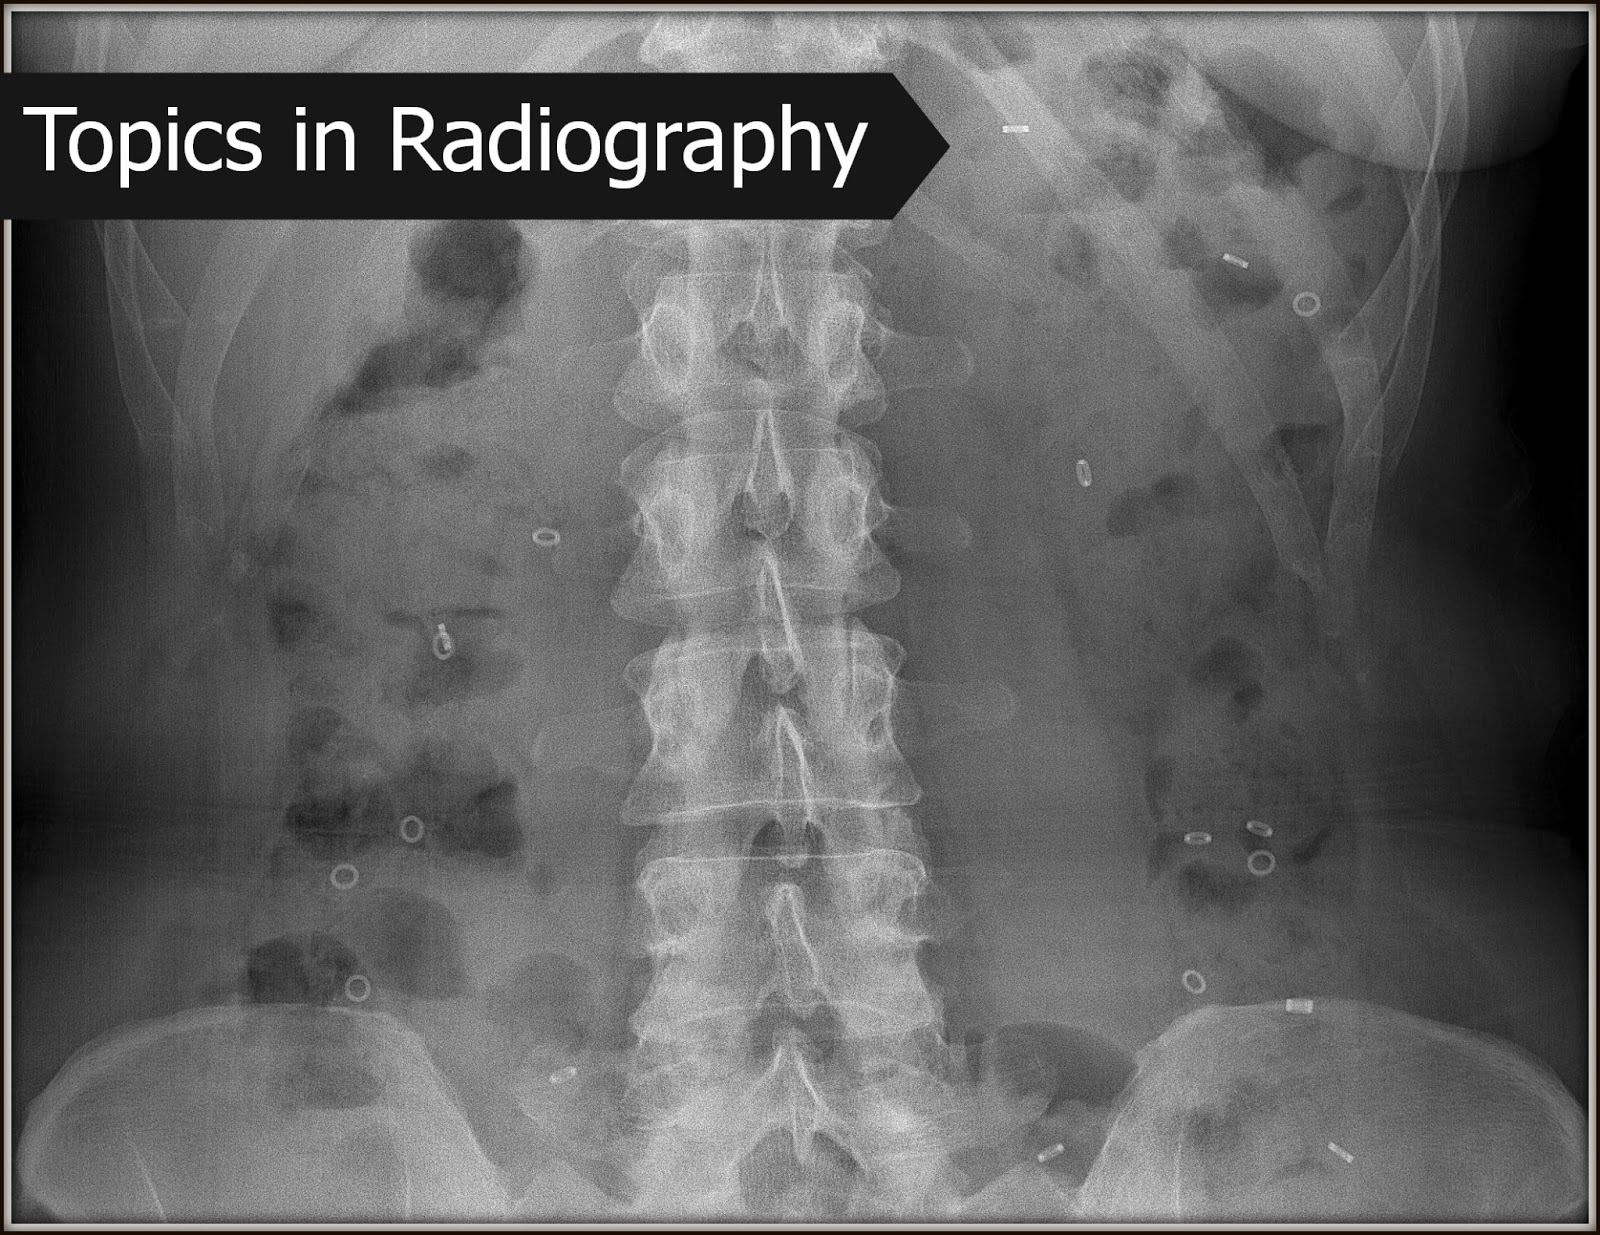

Sitz Marker Colonic Transit Study Day 5 r/Gastroparesis What Is A 5 Day Sitz Marker Study a colonic transit time test is a diagnostic procedure that offers information as to how long it takes for food to travel through your. Patient has a flat plate. radioopaque marker testing distinguishes constipation subgroup such. a colon transit study is a diagnostic test that will allow your doctor to evaluate the function of your colon. A. What Is A 5 Day Sitz Marker Study.

Sitzmarks radiopaque markers 0rings; Drings; and trirings What Is A 5 Day Sitz Marker Study A sitz marker study is most often used with patients who are suffering from chronic constipation. what is a sitz marker study? Patient continues their normal routine as the capsule dissolves and releases the markers inside their digestive tract. a sitz marker study is a test for chronic constipation in adults and children at least two years of. What Is A 5 Day Sitz Marker Study.

Image What Is A 5 Day Sitz Marker Study For the study, the patient swallows a capsule containing. radioopaque marker testing distinguishes constipation subgroup such. a colon transit study is a diagnostic test that will allow your doctor to evaluate the function of your colon. Patient has a flat plate. a colonic transit time test is a diagnostic procedure that offers information as to how long. What Is A 5 Day Sitz Marker Study.

Sitz Marker Test showed 22/24 markers on day 5 r/Constipation What Is A 5 Day Sitz Marker Study a sitz marker study is a test for chronic constipation in adults and children at least two years of age. a colon transit study is a diagnostic test that will allow your doctor to evaluate the function of your colon. our team of specialized doctors, nurses and technologists perform sitz marker studies to see how fast food. What Is A 5 Day Sitz Marker Study.

Sitz Marker Test showed 22/24 markers on day 5 r/Constipation What Is A 5 Day Sitz Marker Study a colon transit study is a diagnostic test that will allow your doctor to evaluate the function of your colon. our team of specialized doctors, nurses and technologists perform sitz marker studies to see how fast food is moving through the intestines. a colonic transit time test is a diagnostic procedure that offers information as to how. What Is A 5 Day Sitz Marker Study.